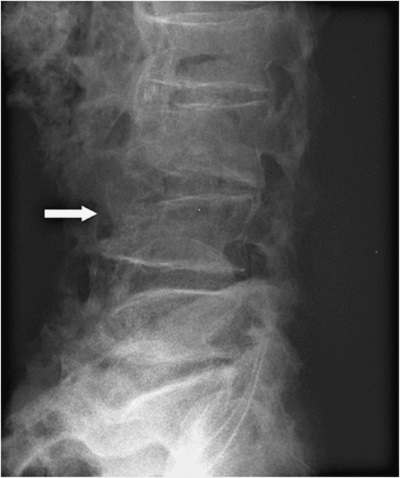

На 3-й день после состоявшегося осмотра участковым врачом выполнена рентгенограмма поясничного отдела позвоночника (см. рис. 1).

Заключение в поликлинике: остеохондроз поясничного отдела позвоночника, остеофиты всех поясничных позвонков. Компрессионные изменения L4.

Рисунок 1. Рентгенограмма поясничного отдела позвоночника

В результате изучения представленной рентгенографии мы констатируем наличие дегенеративно-дистрофических изменений позвоночника в форме остеоартритических изменений (включая деградацию межпозвонкового хряща); возможны протрузии дисков. Следует отметить, что, помимо вышеописанного, обращает на себя внимание остеопороз тел позвонков с компрессионным переломом L4.

Аденома предстательной железы. Синдром частичного дефицита андрогенов. Остеоартрит коленных суставов. Генерализованный остеопороз с патологическими переломами (компрессионный перелом L4, высокий 10-летний риск остеопоротических переломов).